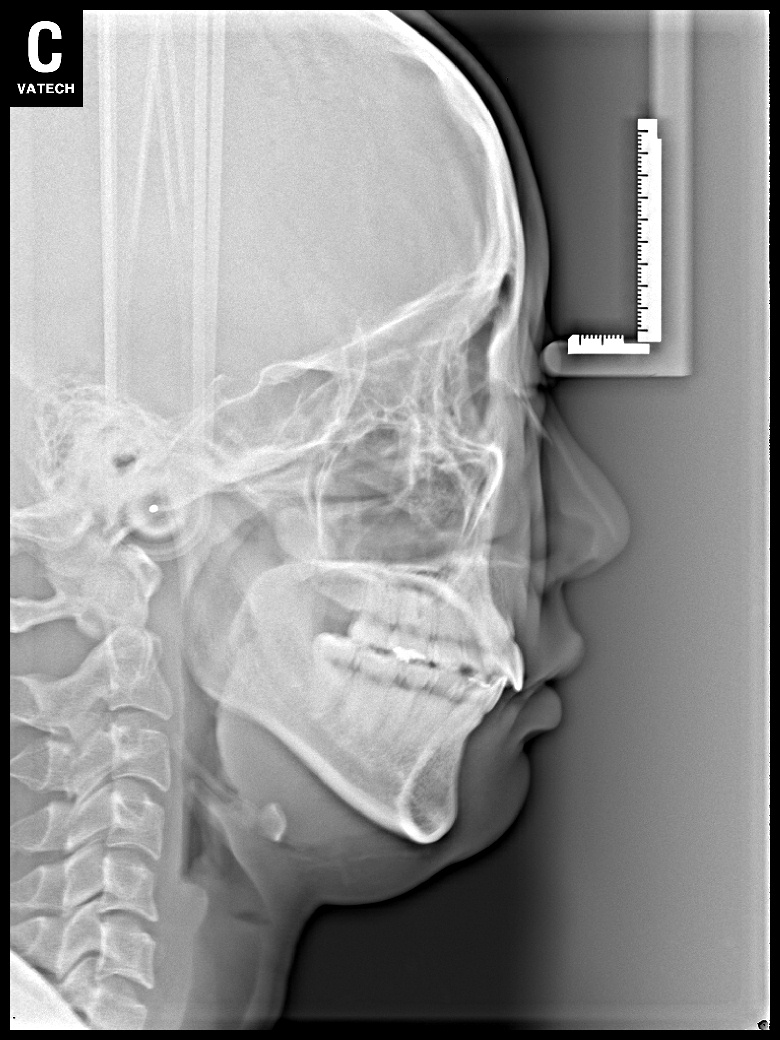

치료 후 사진입니다.